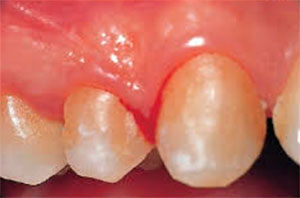

Гінгівіт

Запалення десенной тканини, приватний супутник підліткового віку і вагітних жінок з-за гормональних перебудов організму.

Гінгівіт ділять на кілька типів: катаральний, виразково-некротичний, гіпертрофічний, атрофічний.

Буває гострим і хронічним, загострюється в зимові і весняні місяці ( ясна кровоточать частіше).

Катаральний гінгівіт характеризується:

- запаленням;

- гиперимией;

- набряком;

- кровоточивістю.

Гіпертрофічний гінгівіт характеризується збільшенням десенной тканини, що покриває зуб. Заявляє про себе на останніх стадіях — ясна кровоточать і болять від будь-якого впливу на них.